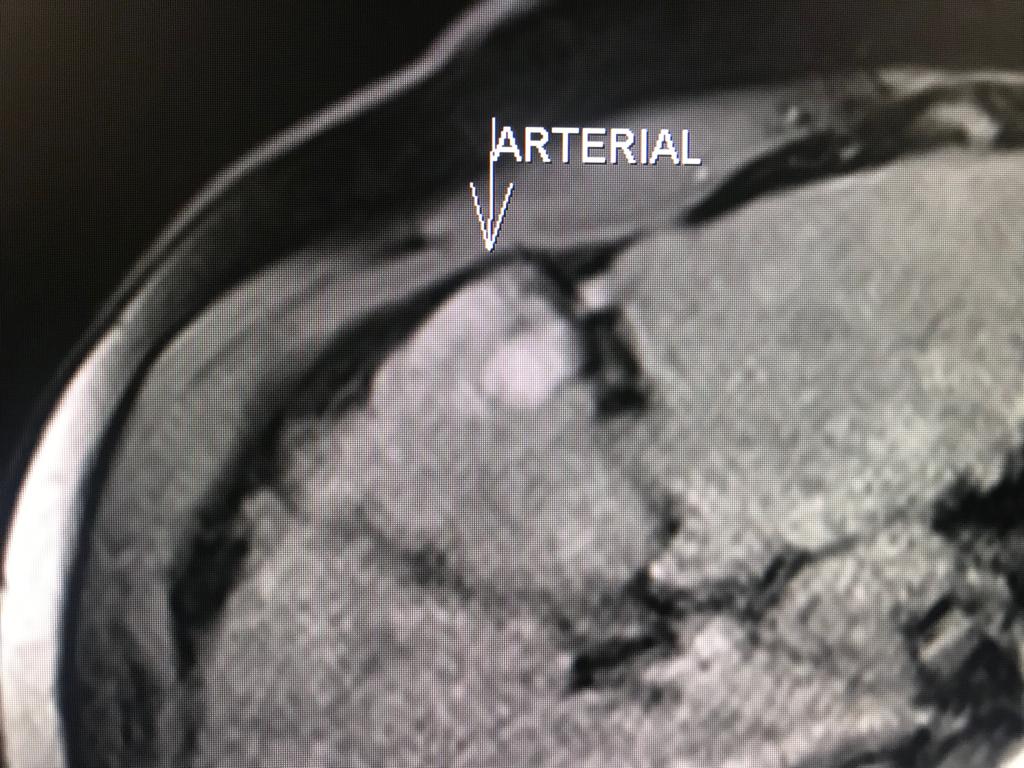

En el presente caso, encontramos una lesión típica de hepatocarcinoma en el segmento 5 ( hiperintensa en T2, restringe en la Difusión con ADC bajo. Realza heterogéneamente postcontraste EV, con wash out y presencia cápsula tardía).

El objetivo es identificar dentro de la multifocalidad de nódulos , un hepatocarcinoma precoz o de pequeño tamaño , cuando la posibilidad de tratamiento con intención curativa es viable , a pesar de la cirrosis.